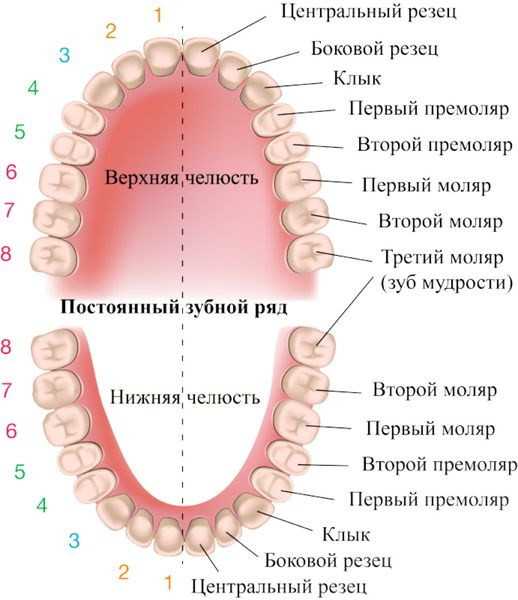

1. Отсутствие жевательных зубов (премоляров и моляров). Это наиболее частая причина асимметрии челюсти. Она развивается, так как после удаления или разрушения этих зубов нижняя челюсть часто смещается в сторону, что в свою очередь влечёт за собой смещение и дисфункцию ВНЧС.

К асимметрии приводит отсутствие только жевательных зубов. Остальные зубы не влияют на этот процесс.

Структура зубных рядов

Когда нет жевательных зубов с одной стороны, человек жуёт пищу на другой стороне, поэтому здесь возникает гипертрофия жевательных мышц (мышцы напрягаются и увеличиваются в размере) [1]. Также патология может развиться, если зубы мудрости прорезались неправильно или у зуба мудрости нет антагониста (симметричного зуба).